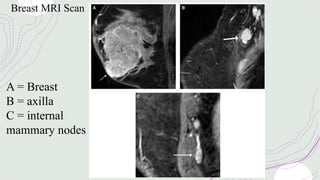

Breast MRI Scan

A = Breast

B = axilla

C = internal

mammary nodes